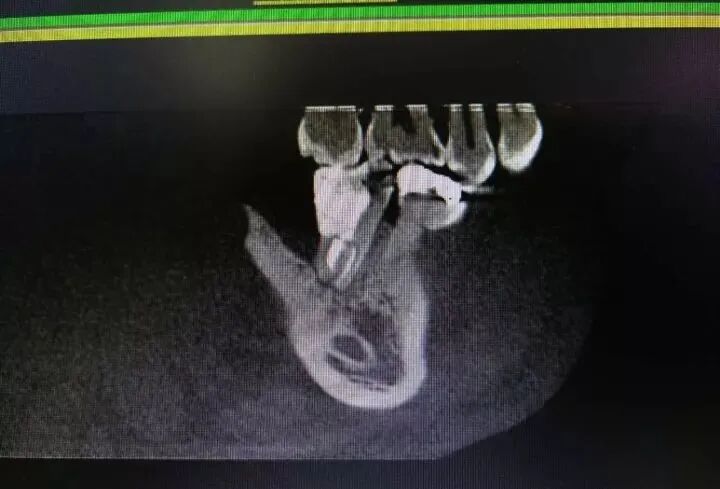

根管治疗前,在X线根尖片初步诊断患牙为牛牙症后,应常规进行CBCT检查,确定根管数目、形态及走向和炎症波及范围,掌握治疗难度,制定相应的治疗方案。

图9 47初诊片